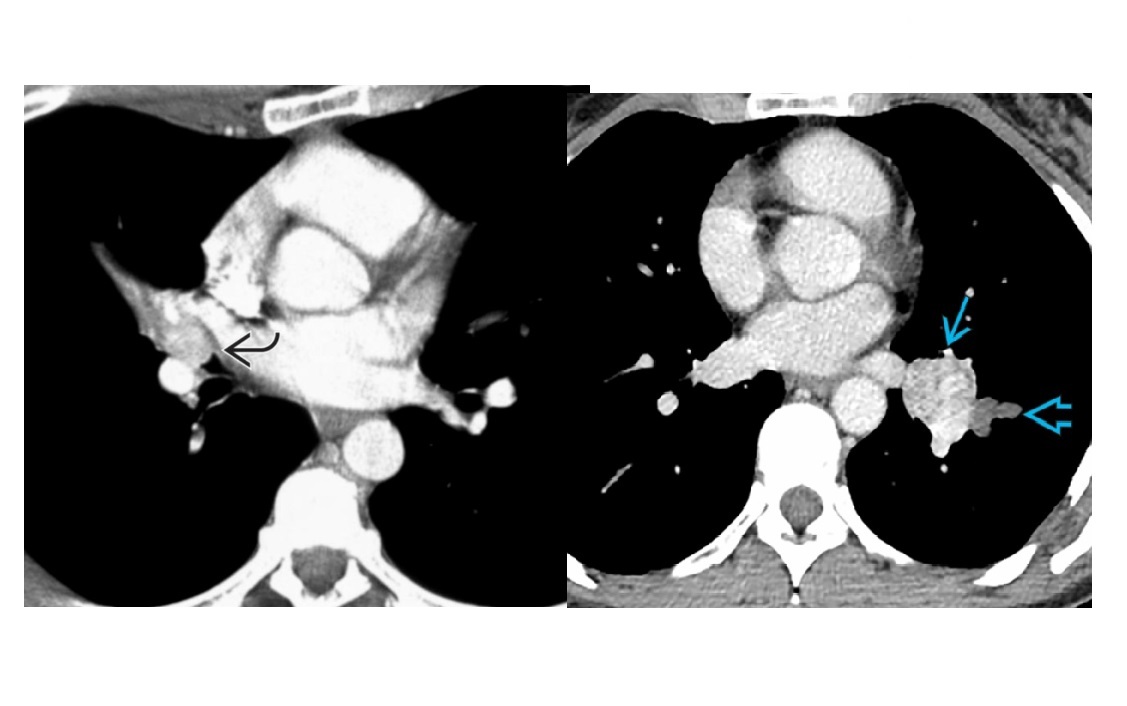

Mucormycosis

Difficult to discern radiologically and clinically from aspergillosis

Can have halo sign but more specific reverse halo sign

unlike COP, peripheral capsule in the reversed halo sign tends to be thicker